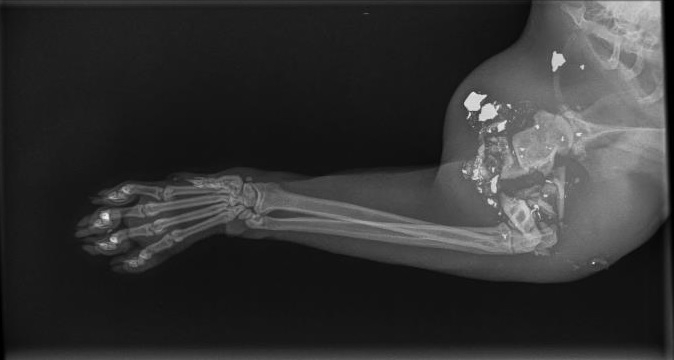

| Dire merci | Juste parce que j'en ai marre, mais marre..... De tirer des radios comme ça.... Nan mais bordel, quoi, pov bêtes.... ![]() Explication de texte: chat errant, nourri par des gens, mais super sympa, qui s'est très probablement fait plomber à bout portant par un ***** de sa **** Humérus complètement explosé, le pauvre chat s'était barré depuis vendredi, revenu aujourd'hui..... heureusement il a des nourrisseurs adorables qui ont accepté le devis d'amputation (qu'on a réduit au minimum qu'on pouvait, pour lui éviter la piqure fatale). Mais on en a facilement 1 par mois en ce moment, c'est l'hécatombe ![]() si ça vous arrive, portez absolument plainte, que les flics se déplacent pour questionner le voisinnage, dans le coin de mes parents, ça avait marché, les tirs ont cessé! Message édité le 11/08/15 à 17:19 |